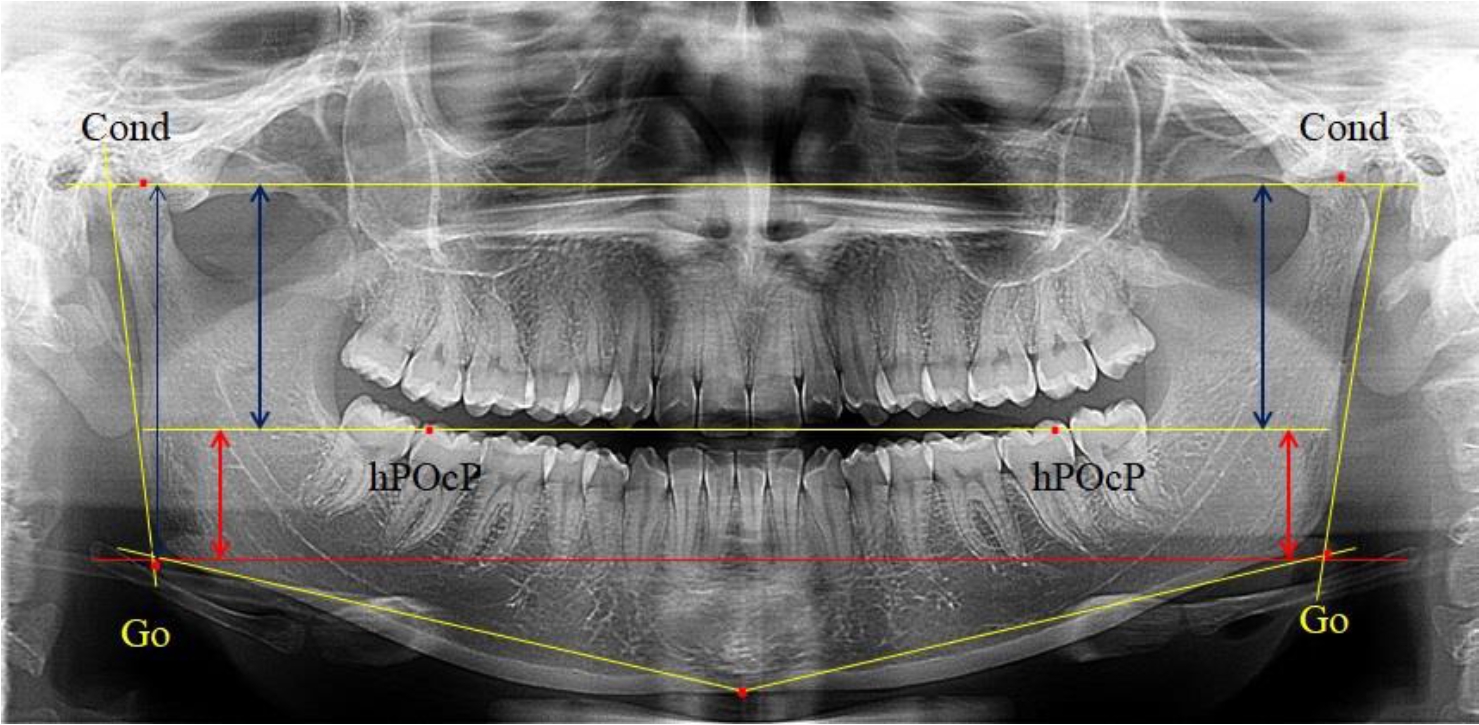

На боковых телерентгенограммах определяли положение верхней точки суставной головки Cond. Касательные линии к ветви и телу нижней челюсти пересекались в точке, которую в клинической практике обозначают как точка угла нижней челюсти или точка гонион Go. Точкой hPOcP обозначали дистальный бугорок нижнего второго моляра вблизи окклюзионного контура коронки, через нее от межрезцовой точки проводили окклюзионную линию, ее продолжали до задней части ветви челюсти. Высоту ветви измеряли как расстояние от угла нижней челюсти до вершины суставной головки Go-Cond. Общую высоту ветви условно делили на 2 части, ее границей служила окклюзионная линия. Верхнюю часть обозначали как окклюзионно-суставная, а нижнюю – как окклюзионно-гониональная.

На ортопантомограмме использовали аналогичные суставные точки Cond на каждой стороне, их соединяли между собой суставной линией Cond-Cond.

Касательная к ветви нижней челюсти соединяла выступающие точку. При построении касательной к телу челюсти проводили в обе стороны линии от точки Gn, расположенной в нижней центральной части подбородочного симфиза, до выступающей нижней точки угла челюсти. Касательные линии при пересечении определяли конструктивную точку гонион Go. Соединение гониональных точек определяло положение гониональной линии Go-Go. При соединении окклюзионных точек hPOcP получали окклюзионную горизонталь (рис. 1). Измеряли расстояние между горизонталями в области ветвей нижней челюсти. Статистический анализ проводили в программе Microsoft Excel. Составляли вариационные ряды с последующим расчетом среднего значения, стандартного отклонения и ошибки среднего ±m. Также оценивали максимальные и минимальные значения величин. Определи относительные величины соотношения верхней и нижней частей ветви нижней челюсти.

Рис. 1. Метод измерения высоты ветви нижней челюсти на телерентгенограмме (а) и ортопантомограмме (б)

3-я подгруппа была с наименьшим количеством анализируемого материала, и здесь было проанализировано 17 комплектов рентгенограмм [(22,97 ± 4,89) %], на которых средняя величина отношения верхней части ветви к нижней составляла 2,45 ± 0,04, что было достоверно больше показателя, полученного по группе в среднем, а также в 1-й и 2-й подгруппе. Визуально параметры ветви отличались от других подгрупп. Высота ветви составляла (57,83 ± 0,89) мм, что было несколько меньше, чем в других подгруппах. Максимальная высота была 64 мм, а минимальная – 53 мм. Высота верхней части составляла (41,03 ± 0,59) мм, что было близким по значениям, полученным в других подгруппах и свидетельствовало о меньшей вариабельности указанного параметра. В то же время высота нижнего отдела ветви была (16,83 ± 0,36) мм и показатель отличался в меньшую сторону, по сравнению с аналогичным размеров в других подгруппах (рис. 4).

Рис. 4. ОПТГ пациента 3-й группы с увеличенным коэффициентом соотношения частей ветви нижней челюсти